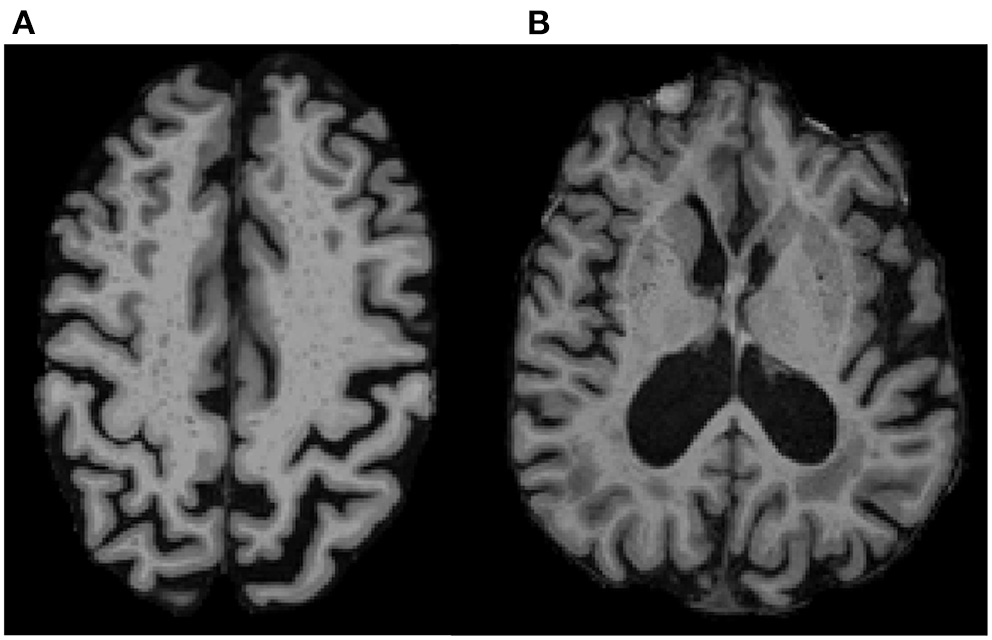

We used a previously validated, visual rating method for quantification of region-specific ePVS burden developed via collaboration between multiple consortia and intended to standardize ePVS assessment across the field of cSVD research (47). The method involves manually counting ePVS on T1 images, with additional reference to T2 FLAIR images. Counts were performed in each hemisphere in a single, axial slice of T1 images, within four regions of interest that are known to have the greatest burden of ePVS (11, 14, 27, 33, 47, 53): the centrum semiovale, 1 cm above the lateral ventricles (Figure 1A); the basal ganglia, in the plane of the columns of the fornix (Figure 1B); the midbrain, at the level of the cerebral peduncles; the hippocampus, at the level of the midbrain.

Figure 1

ePVS Regions of Interest on T1 MPRAGE. Examples show ePVS burden in (A) the centrum semiovale (white matter; 10 mm above the lateral ventricles) and in (B) the basal ganglia (gray matter in the putamen and head of caudate in the plane of the columns of the fornix). A high intra-rater reliability was achieved for ePVS (ICC = 0.9) on a subset of 20 randomly selected participants.